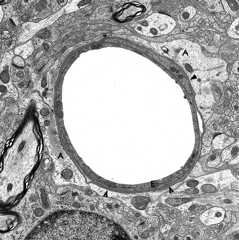

Unlike other organs and tissues, theendothelial cells that line brain capillaries have no fenestrations or pinocytotic (transportation) vesicles and havetightand adherens junctions that almost fuse adjacent endothelial cells. Moreover, these endothelial cells have different receptors and ion channels on their surface facing the lumen than on the surfaces facing the brain, an arrangement that facilitates transcellular transport. This anatomy is the basis of theblood-brainbarrier (BBB). The endothelial cells are surrounded by abasement membrane made up of collagens, laminins, and proteoglycans. A discontinuous layer of pericytes are embedded in this basement membrane.Astrocytic processes rich in Aquaporin 4 (AQP4) cover the capillaries. The space between them and the capillary basement membrane contains a few perivascular macrophages and rare lymphocytes that cross the BBB (passing through endothelial cells rather than between them) and survey this space. The same types of cells are present in the perivascular (Virchow-Robin) space (see below). Brain endothelial cells do not express leukocyte adhesion molecules (LAMs) on their luminal surface and this limits the entry of leukocytes into brain tissue. In non-diseased states, no immune cells or molecules are found deeper in brain interstitial space, resulting in an “immune privileged” status. During development, astrocytes induce brain endothelial cells to develop in this special leak-proof fashion.